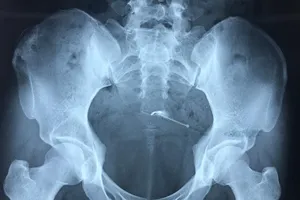

Hi hữu: Vòng tránh thai 'lạc trôi' xuyên thành bàng quang